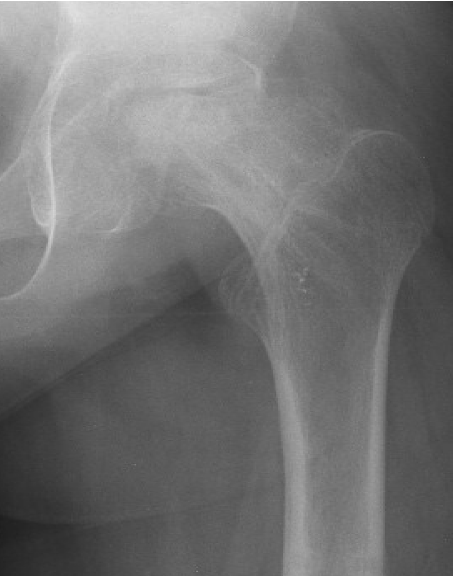

Avascular necrosis

Risk factors

- systematic review of risk factors for AVN in 688 hips

- overall incidence 23%

- risk factors: male / acute slips / severe slips / closed reduction